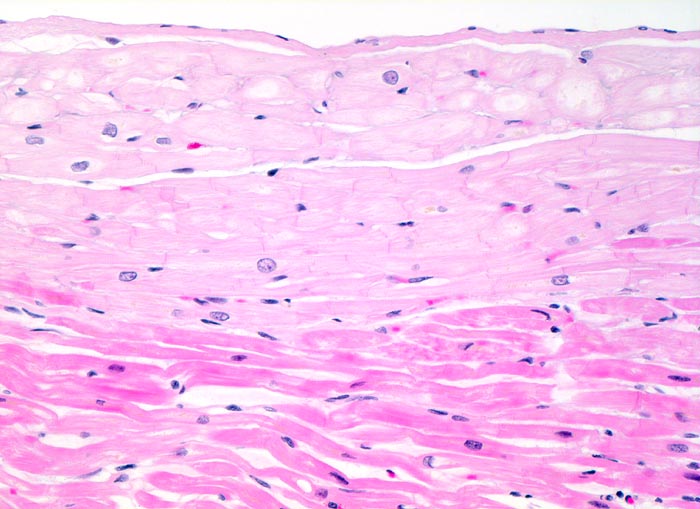

Morphologische Merkmale:

• Herdförmiger Ersatz der Muskulatur durch zellarme rote Kollagenfaserbündel.

• Hypertrophiezeichen der Herzmuskulatur im Randbereich der Narbenareale (verdickte Herzmuskelzellen mit vergrösserten hyperchromatischen Kernen).

• Im untersten Biopsiefragment sind die Narbenareale bandförmig subendokardial verteilt. Zwischen Narbengewebe und Endokard findet sich eine schmale Schicht erhaltener Muskelzellen (Ernährung dieser Zellen per Diffusion direkt aus dem Herzblut).